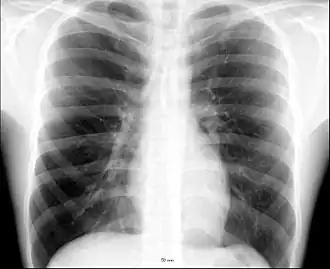

The human thorax includes the thoracic cavity and the thoracic wall. It contains organs including the heart, lungs, and thymus gland, as well as muscles and various other internal structures. The chest may be affected by many diseases, of which the most common symptom is chest pain.

.jpg)

Different types of diseases or conditions that affect the chest include pleurisy, flail chest, atelectasis, and the most common condition, chest pain. These conditions can be hereditary or caused by birth defects or trauma. Any condition that lowers the ability to either breathe deeply or to cough is considered a chest disease or condition.

The major pathophysiologies encountered in blunt chest trauma involve derangements in the flow of air, blood, or both in combination. Sepsis due to leakage of alimentary tract contents, as in esophageal perforations, also must be considered. Blunt trauma commonly results in chest wall injuries (e.g., rib fractures). The pain associated with these injuries can make breathing difficult, and this may compromise ventilation. Direct lung injuries, such as pulmonary contusions (see the image below), are frequently associated with major chest trauma and may impair ventilation by a similar mechanism.